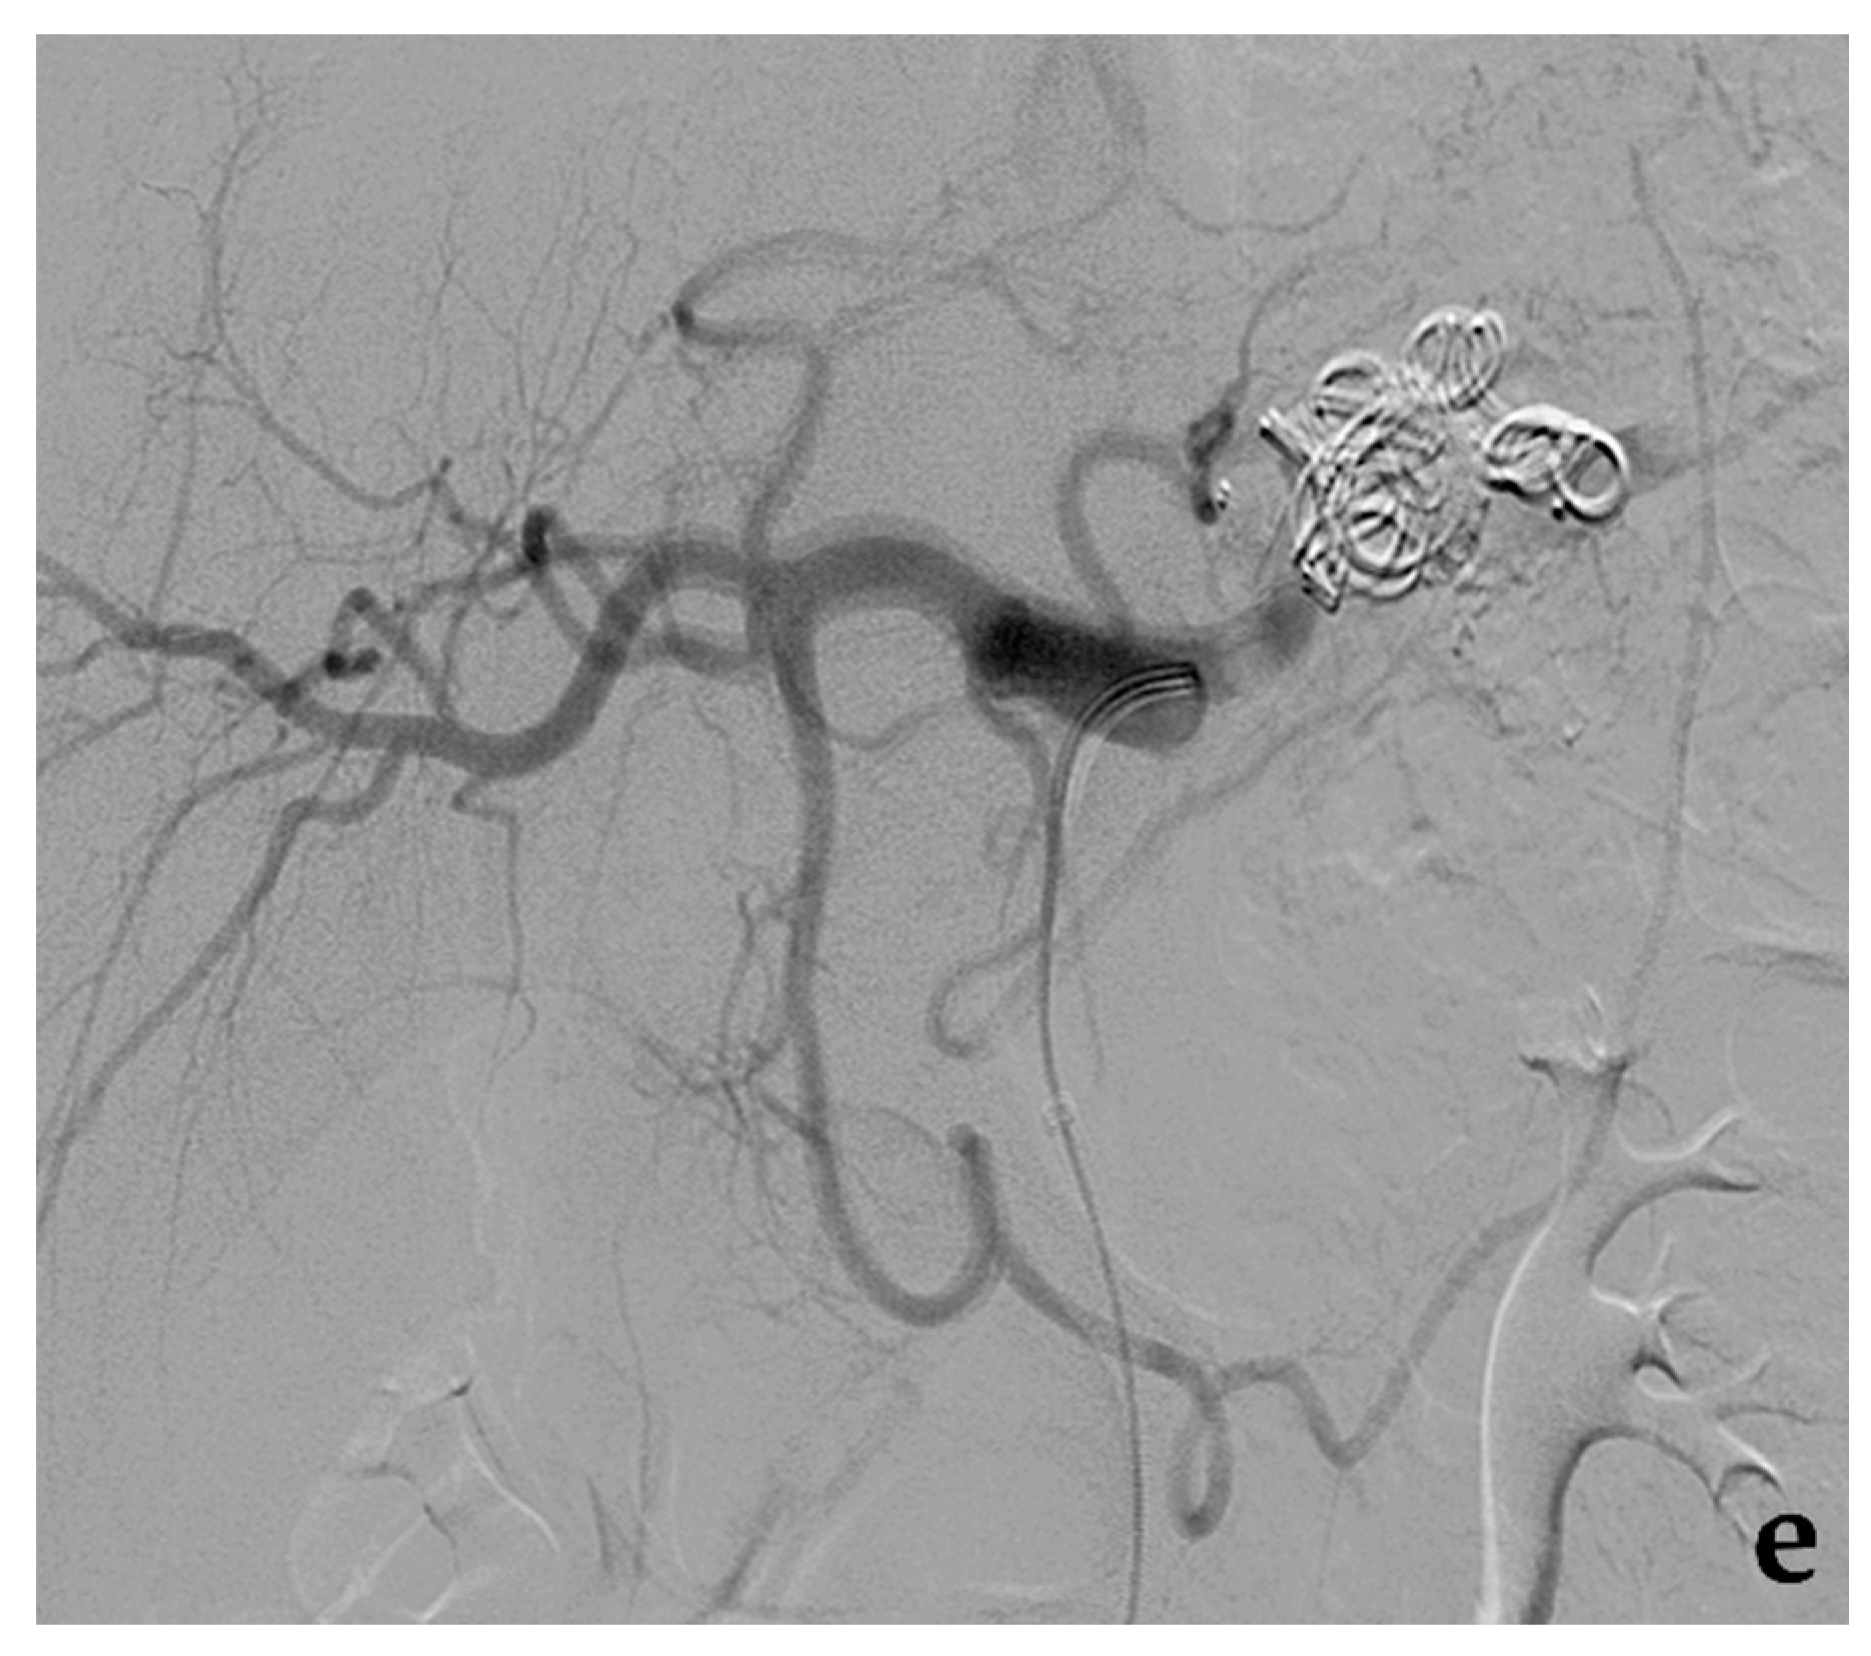

3.5. Embolization with Non-Adhesive Liquid Embolic Agents (Onyx, Squid, Phil)

- Venturini, M.; Lanza, C.; Marra, P.; Colarieti, A.; Panzeri, M.; Augello, L.; Gusmini, S.; Salvioni, M.; De Cobelli, F.; Del Maschio, A. Transcatheter embolization with Squid, combined with other embolic agents or alone, in different abdominal diseases: A single-center experience in 30 patients. CVIR Endovasc. 2019, 2, 8. [Google Scholar] [CrossRef]

- Venturini, M.; Marra, P.; Augello, L.; Colarieti, A.; Guazzarotti, G.; Palumbo, D.; Lanza, C.; Melissano, G.; Chiesa, R.; De Cobelli, F. Elective embolization of splenic artery aneurysms with an ethylene vinyl alcohol copolymer agent (Squid) and detachable coils. J. Vasc. Interv. Radiol. 2020, 31, 1110–1117. [Google Scholar] [CrossRef] [PubMed]

- Venturini, M.; Della Corte, A.; Lanza, C.; Fontana, F.; Chiesa, R.; De Cobelli, F. Embolization of 2 coexisting intraparenchymal renal artery aneurysms with an ethylene vinyl alcohol copolymer agent (Squid) and coils. Cardiovasc. Interv. Radiol. 2020, 43, 942–944. [Google Scholar] [CrossRef] [PubMed]